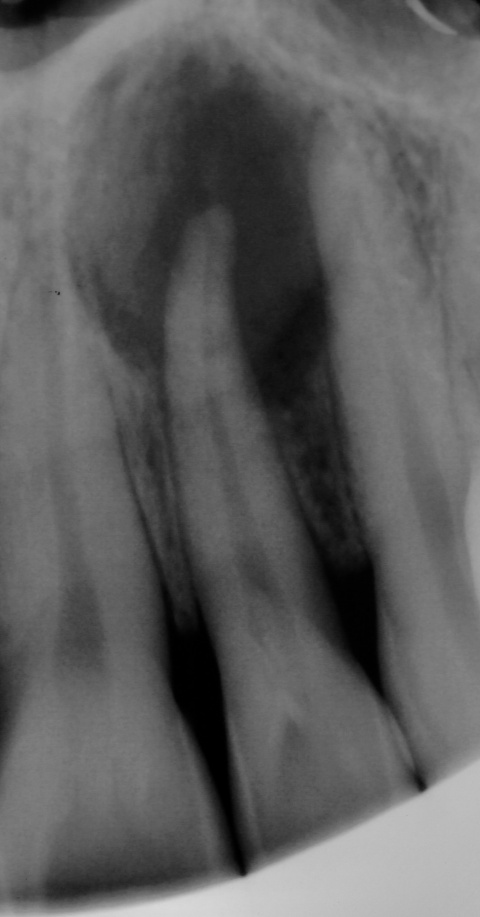

Zahn 22, zudem zeigen sich Kalzifizierungen im

Bereich des Wurzelkanaleinganges.

Eine 39-jährige Soldatin stellte sich im Januar 2020 mit Druckbeschwerden Regio 22 in unserer Abteilung vor. Wie auch in der vorangegangenen Falldarstellung konnten die Beschwerden mit Druck auf das Vestibulum verstärkt werden. Der Perkussionstest fiel deutlich positiv, der Vitalitätstest hingegen negativ aus. Eine erhöhte Lockerung des Zahnes lag, trotz des eindrucksvollen Röntgenbefundes, nicht vor. Erste Beschwerden traten laut Aussage der Patientin bereits 2014 auf. Das zu diesem Zeitpunkt angefertigte Röntgenbild zeigte keinen signifikanten pathologischen Befund, woraufhin die Situation weiterhin beobachtet wurde. Das aktuell angefertigte Röntgenbild zeigte eine umfangreiche periapikale Osteolyse, welche sich bis zu den Wurzelspitzen 21 und 23 erstreckte. Der Vitalitätstest der beiden benachbarten Zähne fiel positiv aus.

Nach Aufklärung der Patientin wurde die primäre Wurzelkanalbehandlung eingeleitet. In einem ersten Schritt erfolgte die Isolierung des Zahnes mittels Kofferdam und die Trepanation unter mikroskopischer Sicht. Nach durchgeführter endodontischer Behandlung kam Ledermix® (Riemser Pharma GmbH, Greifswald) als medikamentöse Einlage zum Einsatz. Zur Kontrolle und Medikamentenwechsel wurde ein Termin eine Woche später vereinbart. Bei erneuter Vorstellung war die Patientin annähernd beschwerdefrei und die Fistelung in Ausheilung begriffen. Erneut wurde der Wurzelkanal mit 10 ml 3,5 %-igen Natriumhypochlorit gespült und ein Calciumhydroxidpräparat (Ultracal XS der Firma Ultradent Products GmbH, Köln) eingelegt.

Zwei Wochen später (eine Woche vor dem regulären Termin zur Wurzelfüllung) stellte sich die Patientin erneut mit Beschwerden sowie erstmal aufgetretener Fistelung in unserer Abteilung vor. Nach eingehender Aufklärung entschlossen wir uns zusammen mit der Patientin, die endodontische Therapie kombiniert chirurgisch zu unterstützen. Für die nächsten zehn Tage schirmten wir sie medikamentös ab (Amoxiclav 1000 mg der Firma 1A Pharma GmbH, Unterhaching), so dass die Einnahme des Antibiotikums den operativen Eingriff zusätzlich flankierte.

Der chirurgische Eingriff erfolgte ohne Entfernung der Wurzelspitze des Zahnes 22. Laut der bereits erwähnten Untersuchung von Song et al.[5] lag unter anderem eine Ursache für den Misserfolg einer durchgeführten Wurzelkanalbehandlung zu 8,7 % in einer komplexen anatomischen Struktur und zu 19,7 % in einem übersehenen Wurzelkanal. Das mechanische und chemische Aufbereiten des hier vorgefundenen Wurzelkanals sowie die Obturation waren jedoch auch ohne Resektion der Wurzelspitze problemlos möglich. Wie in Abbildung 11 zu sehen, kam es zu einer intendierten Überfüllung des Wurzelkanals. Daher ist von einer Nischenbildung im apikalen Bereich nicht auszugehen. Das überpresste Wurzelfüllmaterial konnte im Rahmen des anschließenden chirurgischen Eingriffs zuverlässig entfernt werden. Eine zusätzliche Wurzelspitzenresektion hätte in diesem Fall keinen entscheidenden Vorteil gebracht. Kritisch hingegen ist zu betrachten, ob wir der kombiniert endodontisch-chirurgischen Therapie nicht gleich zu Anfang der Behandlungsplanung den Vorzug hätten geben sollen.

des Zahnes 22, das überpresste Wurzelfüllmaterial

zeigt die vollständige Erfassung des Wurzelkanalsystems.